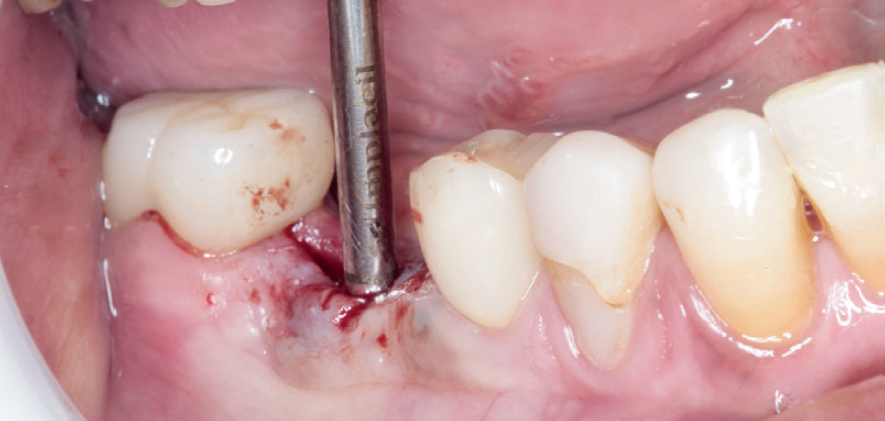

Para a instalação do implante imediato de corpo cônico cone-morse (Maestro, 4 mm x 9 mm, Implacil De Bortoli – São Paulo, Brasil), iniciou-se a fresagem de 9 mm com a fresa lança helicoidal 2.0, seguindo com a fresa cônica 3,5 mm x 9 mm com inclinação para mesial, na região mais centralizada entre a vestibular e a lingual do septo inter-radicular. Com o uso do Túnel Check Cônico 4.0 – instrumental que permite realizar a medição da profundidade da fresagem e sua inclinação –, verificou-se o paralelismo da perfuração para inserção do implante dentário (Figura 4). Em seguida, o implante dentário foi inserido com travamento final de 20 Ncm e recebeu o parafuso de cobertura correspondente (Figuras 5 e 6).